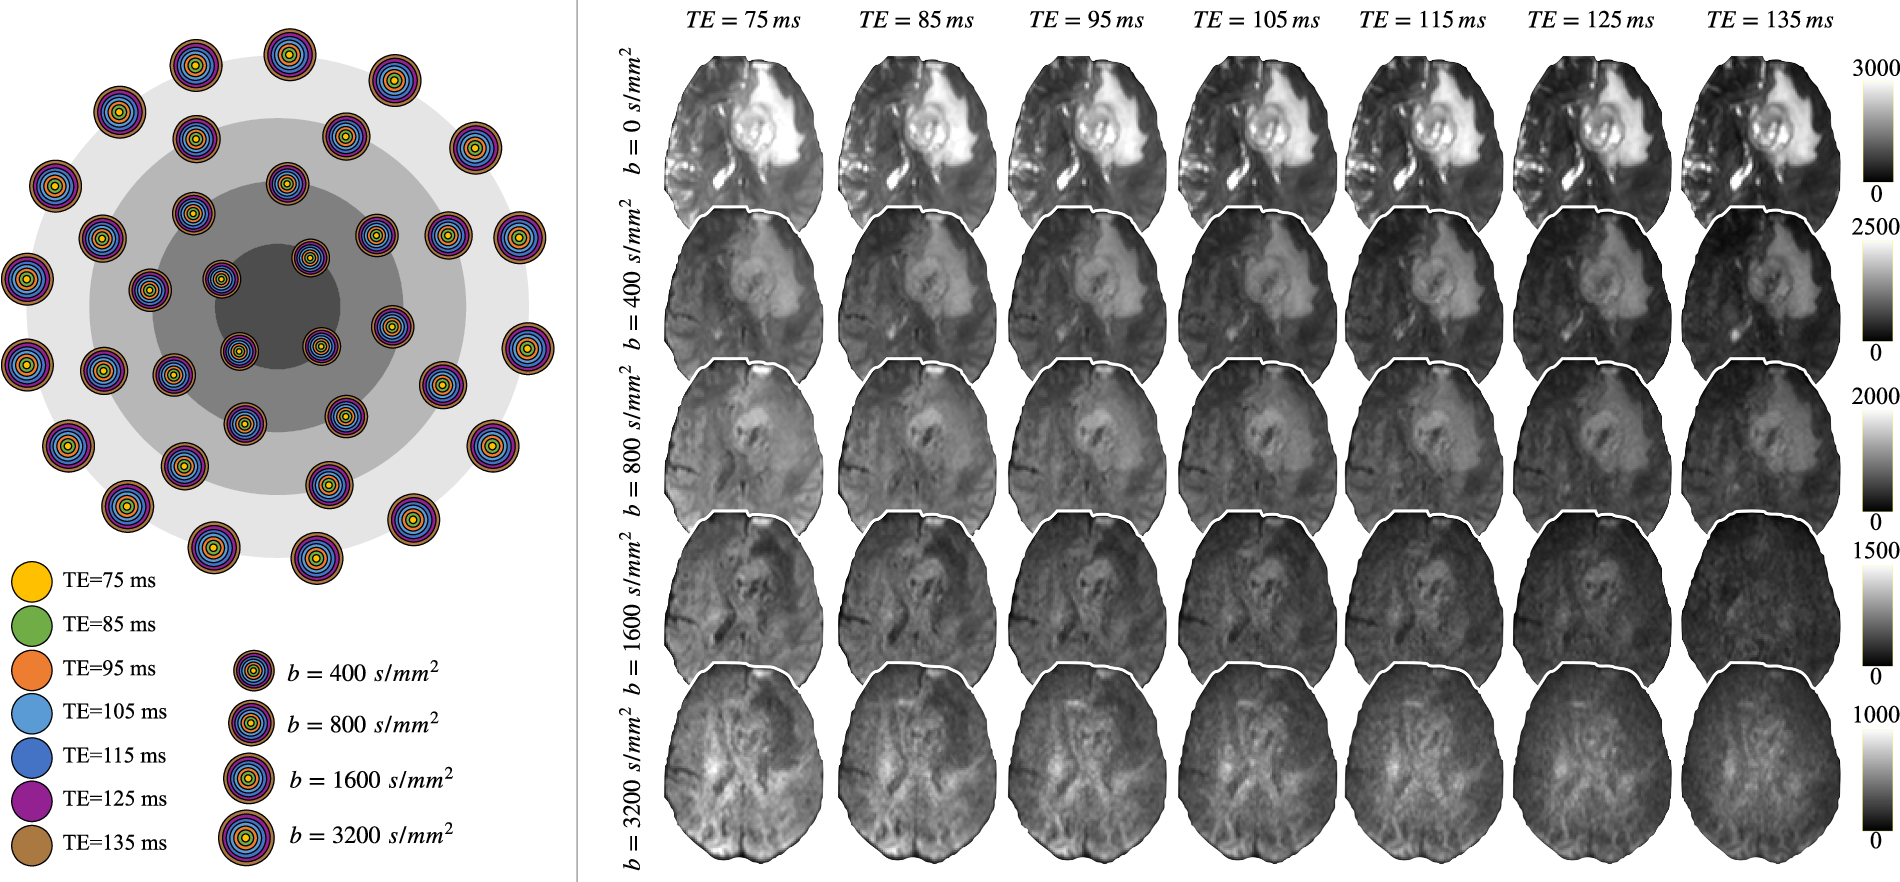

An open relaxation-diffusion MRI dataset in neurosurgical studies

Ye Wu, Xiaoming Liu, Yunzhi Huang, Tao Zhou, Fan Zhang

Exploring the Potential Applications of Relaxation-Diffusion Spectrum Imaging in Neurosurgical Studies

Ye Wu, Xiaoming Liu, Peng Sun, Yizhe Zhang, Jiaolong Qin, Tao Zhou